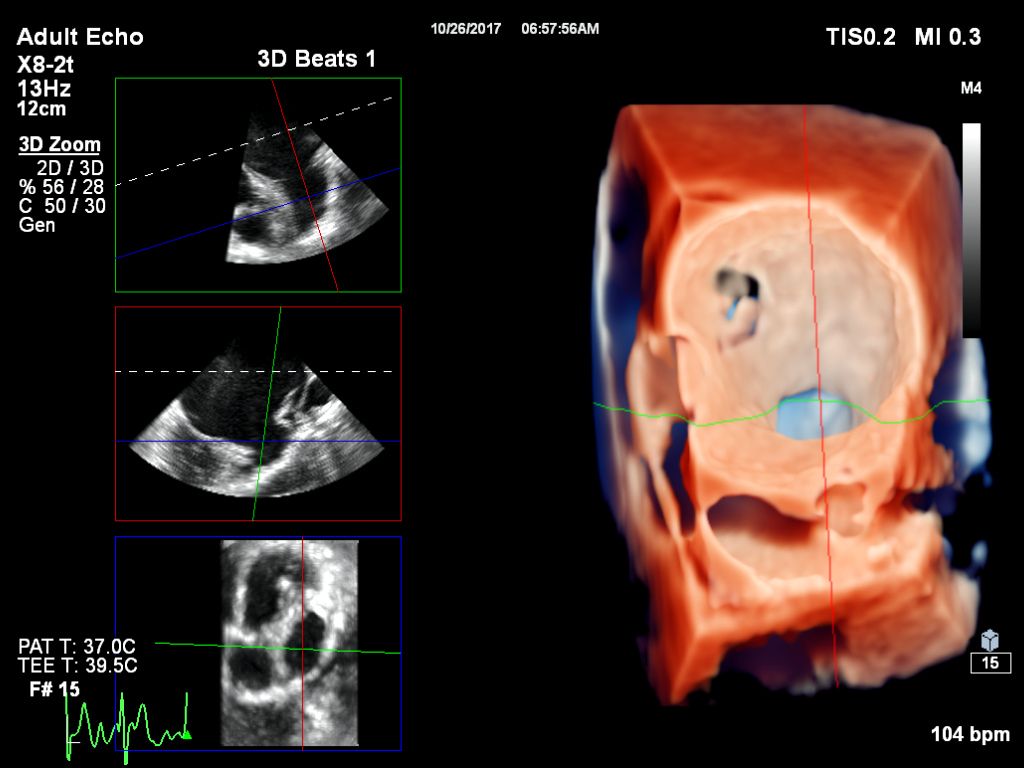

次世代のリアルタイム3d心エコー装置の開発 技術解説 Geヘルスケア ジャパン株式会社 Innavi Suite

臨床3次元心エコー 症例から学ぶ2次元心エコーとの比較 塩田 隆弘 本 通販 Amazon